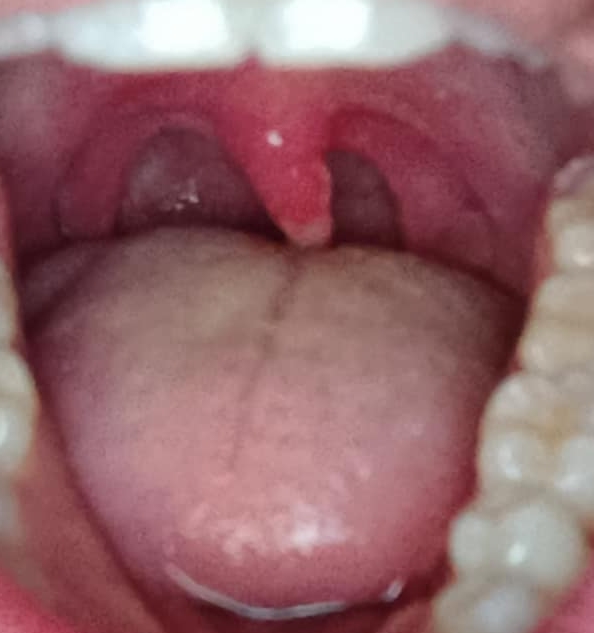

Can anyone tell me what the fuck is wrong with my uvula? It's hard to tell from the picture but in real life it looks like it's melted through to the inner part of it and it's yellow and weird. Also the bottom is swollen and yellow too, I woke up like this

What if I haven't had sex in like 4 years? I did get misdiagnosed with syphilis like 15 years ago, maybe I've had it this whole time? Also I saw a doctor, I've had a swollen throat for a few days but just looked at it for the first time. They just said it wasn't covid or strep, they didn't say it look like a fuckin maggot attached to my uvula and that it looked dissolved